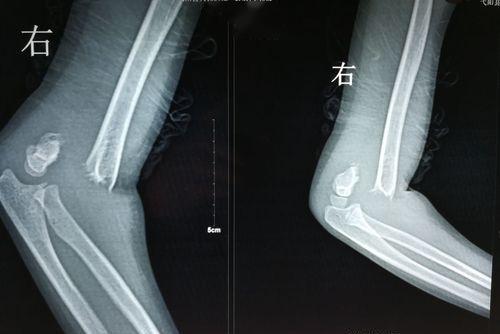

伸直型肱骨髁上骨折的症状根据伤后是否有移位骨折而有所不同。无移位骨折时,肘部肿胀、疼痛,肱骨髁上有明显的压痛、功能障碍,X线可见骨折裂缝;有移位骨折时,肘部肿痛较明显,肿胀严重时可出现张力性水疱,肘后突起呈靴形畸形,但肘后三角关系仍保持正常,X线可见骨折断端移位。

伸直型肱骨髁上骨折,受伤时间短,局部肿胀轻,没有血液循环障碍者,可去骨科进行手法复位外固定。手法复位失败,伴有神经血管损伤时,可以采取手术治疗,术后应严密观察肢体血液循环及手的感觉、运动功能。抬高患肢,早期可进行手指及腕关节的屈伸活动,有利于减轻水肿。